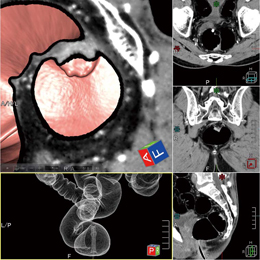

また,2体位表示は,体位により経常の変化するポリープ病変の観察や残渣の移動確認も有用である。以下に,2体位表示機能の使用例を示す。仰臥位画像で観察を進めていくと,残液により視覚が確保されない部分が現れた。ここで比較画面に切り替えると,腹臥位画像が仰臥位の位置に合わせて表示される。視点位置を連動させて観察を行うことで,仰臥位では残液に隠れていた部分の情報が腹臥位画像より得られる(図7)。 |

図7 2体位表示

上段:仰臥位 下段:腹臥位 |